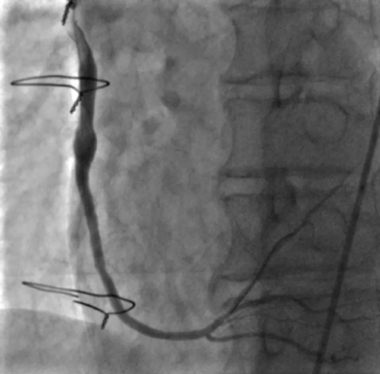

75岁的李先生在20年前行冠状动脉搭桥手术,撘了3根桥。近2年反复胸闷胸痛发作,最近3月症状加重,快走或上楼后就会出现明显的胸痛伴背痛,就诊于我院心内科。行冠状动脉造影检查,可以看到冠状动脉原有的三根血管前降支,回旋支,右冠状动脉均有弥漫性的狭窄阻塞:右冠状动脉远端闭塞,前降支的乳内动脉桥,回旋支的大隐静脉桥血管通畅,但右冠状动脉桥血管远端吻合口闭塞且伴有血栓形成,可见右冠桥血管内明显的造影剂滞留。

经过充分的准备,在心内科主任刘巍教授的指导下,介入经验丰富的术者心内科主范军任医师和助手兰永昊医生对静脉桥血管进行介入治疗。考虑桥血管病变的特殊性,尤其是静脉桥血管,盲目扩张很容易导致更严重的并发症出现。仅从造影来看,无法完全明确桥血管内病变性质特点,在导丝通过闭塞血管段后,使用血管内超声进行检查可见到,桥血管远端吻合口部位为纤维组织增生为主,桥血管内无明显血栓。然而球囊扩张吻合口时由于病变坚硬,多次出现球囊滑脱难以扩张成功,刘巍与范军根据病变特点,决定在准分子激光对桥血管进行充分消蚀的基础上,再次扩张血管。激光消蚀后,血流明显改善,狭窄程度也有减轻,之后再次使用球囊扩张可见扩张效果非常满意,基本无残余狭窄,植入药物球囊,未植入支架,最终效果非常满意。